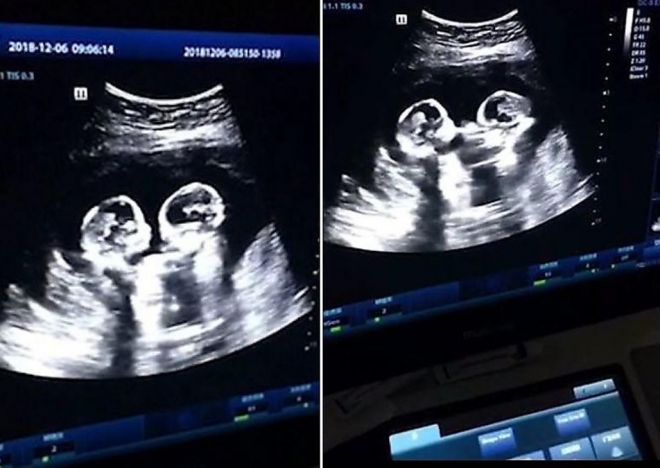

Այսօր ՈՒՁՀ-ն համարվում է հղի կանանց համար ամենակարևոր գործընթացներից մեկը։ Նախ, դրա միջոցով Դուք կարող եք իմանալ՝ այդյո՞ք պտուղը լավ է զարգանում, թե՞ կան որոշակի խնդիրներ։ Երկրորդը՝ հնարավորություն կունենաք տեսնել, թե ինչով է Ձեր փոքրիկը զբաղվում այդտեղ։

ՈՒՁՀ-ն ապագա ծնողների համար ամենահուզիչ պահերից մեկն է, քանի որ նրանք առաջին անգամ ծանոթանում են փոքրիկի հետ։ Պետք է նշել, որ ուլտրաձայնայկն հետազոտության որոշ կադրեր այնքան զվարճալի ու հետաքրքիր են ստացվում, որ ծնողները դրանք հրապարակում են համացանցում։